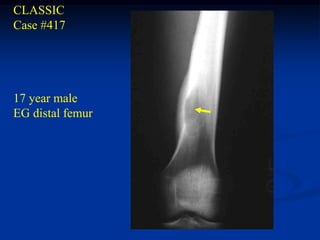

CLASSIC

Case #417

17 year male

EG distal femur

Lateral view